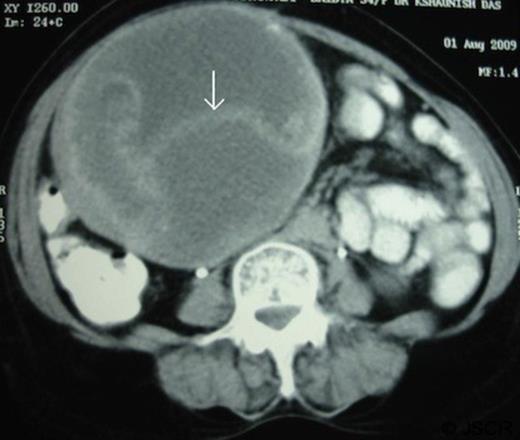

A 54-year-old woman presented with a 2-years history of dull aching pain in the upper abdomen and 1 year history of an abdominal swelling. She underwent open cholecystectomy 7 years back. She developed fever and purulent discharge from the wound in the immediate postoperative period which was treated conservatively. On examination a large non-tender mass with restricted side to side mobility was found in the right hypochondrium extending up-to the right lumber region. Blood investigations revealed hemoglobin of 8.5Gm/dl, leukocyte count of 9600/mm3, serum bilirubin of 2.9 mg/dl and alkaline phosphatase of 507 U/L. The plain abdominal radiography did not show any sign of a radio-opaque marker in the abdomen. However, contrast enhanced abdominal computerized tomography revealed a 15×12x10 cm round well-defined soft-tissue mass with multiple septae. The wall of the lesion and septae showed mild contrast enhancement (Figure-1).

CT scan abdomen (both oral and intravenous contrast) showed a mass in right upper quadrant with displacement of gut loops towards the left. The mass showed contrast enhanced internal septa (white arrow)

A radio-opaque material was seen in the lesion raising the suspicion of a foreign body. Common bile duct was dilated and contained a stone which was removed endoscopically. At exploration, a large globular lesion was found which was densely adhered to the adjacent structures (anterior abdominal wall, omentum, transverse colon, and antrum of the stomach). En-bloc resection of the mass along with the adhered transverse colon was done (Figure-2). Cut section of the mass showed a large surgical sponge and a foreign body within it (Figure-3).The patient had an uneventful recovery and she was well at 19-month follow-up.